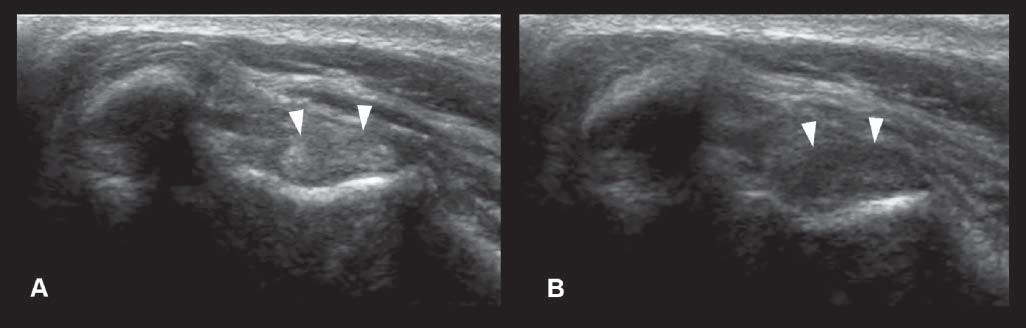

Edgeshadowing appearsasdiscrete,triangular zonesoflowamplitude,attheedgeofacurved structure(Figure1.14A).When,thecurvedstructure isfluidfilled,theedgeshadowingartifactbordersthe enhancementartifact.Thistypeofrefractiveshadowingcanbeconfusing,especiallywhenitoccursatthe

cranialaspectofafluidfilledbladder,andappearsas a“defect”ofthewall(Figure1.14B).

Figure1.14. Edgeshadowingandrefraction.A,B: Edgeshadowing(arrowheads)isoftenseeninprolongationoftherenal pole.LK,leftkidney. C: Thecurvatureofthebladderwallcausesbeamrefraction,whichresultsinanacousticshadow(arrowheads)inthisdogwithechogenicperitonealeffusion(*).Aholeinthebladderwall(arrow)isartifactuallycreated. D: Inanother dogwithcardiactamponadeandmarkedperitonealeffusion(*),theartifactualholeinthebladderwall(arrow)isattenuated byrepositioningthetransducerwithadifferentangulation.